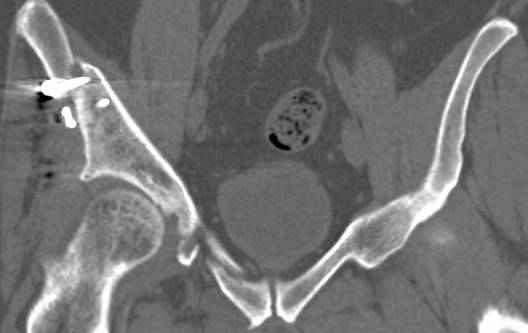

высылаю дополнительно сканы.

Чего-либо принципиально нового мы не увидим на стандартных проекциях. Да, проекции делать надо. Это принятый алгоритм обследования. Но, представленные 3D и срезы вполне достаточны для клинического случая и понимания.

По отдельным срезам и тем более по реконструкции трудно судить о сращении крыла и задней колонны с осевым скелетом.

В большинстве случаев при двухколонных переломах

в итоге получается прочный бублик с дыркой. При эндопротезировании в дырку помещается головка, а чашка должна неплохо заклиниться в бублике.

Главное, чтобы бублик не был разорван, что не очень понятно на представленных снимках.

Хорошо бы на рентгенограммы взглянуть и побольше срезов по своду. С каким отломком головка контактирует и как ее состояние.

Дополнительные сканы